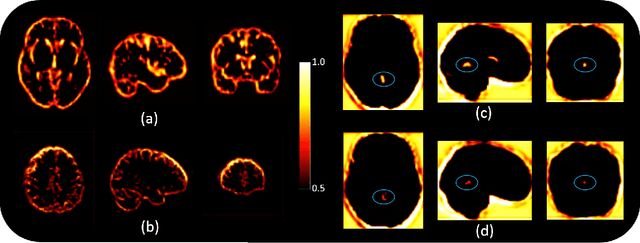

Abstract:Medical imaging datasets are inherently high dimensional with large variability and low sample sizes that limit the effectiveness of deep learning algorithms. Recently, generative adversarial networks (GANs) with the ability to synthesize realist images have shown great potential as an alternative to standard data augmentation techniques. Our work focuses on cross-modality synthesis of fluorodeoxyglucose~(FDG) Positron Emission Tomography~(PET) scans from structural Magnetic Resonance~(MR) images using generative models to facilitate multi-modal diagnosis of Alzheimer's disease (AD). Specifically, we propose a novel end-to-end, globally and locally aware image-to-image translation GAN (GLA-GAN) with a multi-path architecture that enforces both global structural integrity and fidelity to local details. We further supplement the standard adversarial loss with voxel-level intensity, multi-scale structural similarity (MS-SSIM) and region-of-interest (ROI) based loss components that reduce reconstruction error, enforce structural consistency at different scales and perceive variation in regional sensitivity to AD respectively. Experimental results demonstrate that our GLA-GAN not only generates synthesized FDG-PET scans with enhanced image quality but also superior clinical utility in improving AD diagnosis compared to state-of-the-art models. Finally, we attempt to interpret some of the internal units of the GAN that are closely related to this specific cross-modality generation task.